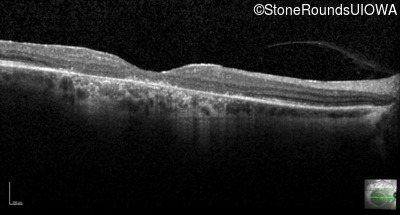

Optical Coherence Tomography - Right - 10/100 -2 sc

Exemplar / OCT Stack

OCT Stack

Optical Coherence Tomography - Left - 10/125 -2 sc